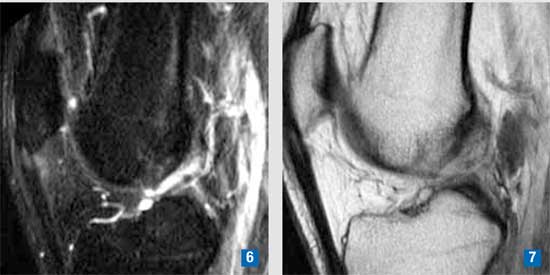

Il paziente è sdraiato sul lettino: in posizione prona o supina a seconda della struttura tendinea da esaminare. Previa preparazione del campo sterile che prevede l’utilizzo di presidi sterili anche per la sonda ecografica, viene eseguita anestesia locale loco-regionale perifocale alla zona tendinea da infiltrare con 5-10 cc di bupivacaina al 2%. La somministrazione endotendinea di PRP viene eseguita sotto guida ecografica con un ago da 18 G nelle aree alterate e defibrillate del tendine precedentemente studiate con esame ecografico e risonanza magnetica. (Figg. 4-7)

| Figura 6-7 - Stesso caso. Risonanza magnetica: sequenze STIR e SET1: area di alterato segnale a carattere iperintenso in sede infratendinea nella sede prossimale del tendine e nei tessuti limitrofi. |